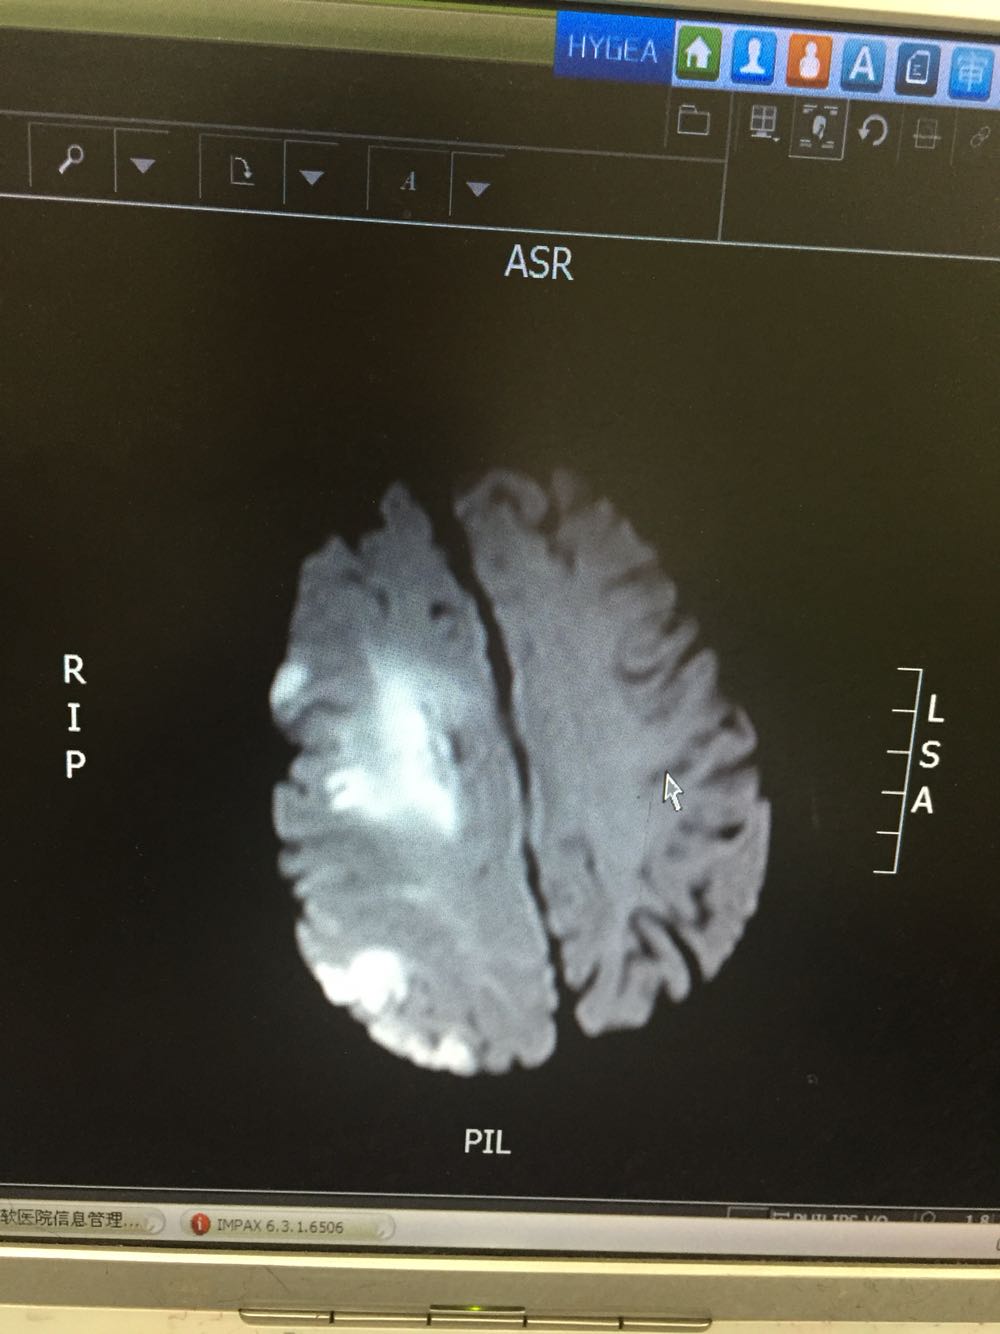

患者入院治疗后症状一度好转,左侧肢体肌力3级+,于入院后第二日病情突然加重,伴意识障碍,头DWI示:脑梗死伴脑出血 右侧大脑中动脉闭塞。停止当前治疗方案,脱水脑保护,营养神经对症治疗。入院后第5日复查头CT示:右侧大面积脑梗死,脑出血吸收期,伴左侧枕叶脑出血。患者左侧枕叶脑出血不好解释,能否是搬运及护理时外伤所致?